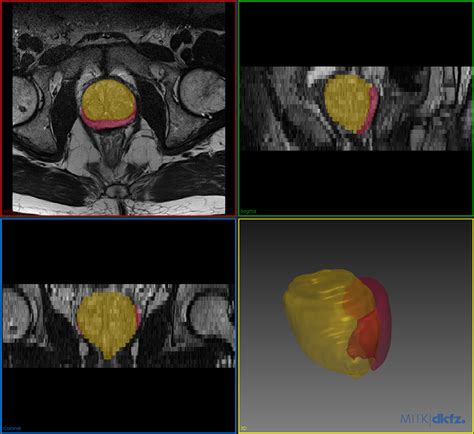

OSCI Imaging offers various services such as: Image Acquisition, Image Processing, and Image Analysis. Image acquisition is the process of getting a visual representation of the subject. Image processing involves modifying images to improve the analysis. This can include removing noise, enhancing contrasts, or other adjustments. Image analysis is the process of extracting the required information from the images. OSCI Imaging deals with the challenges of handling, analyzing, and interpreting scientific image data. The field of OSCI Imaging is broad, and it includes many techniques. For example, Image segmentation, which is used to divide an image into meaningful parts, and feature extraction, which involves identifying the image features of interest, can improve image quality. It uses tools and methods to convert raw images into useful data that can be interpreted and analyzed. OSCI Imaging, by focusing on imaging-related issues and giving tools, improves the quality and the usage of scientific images.

OSCI Imaging is a core element in a variety of scientific fields, and it is a key instrument in research. OSCI Imaging supports research areas, including: Medical imaging (CT scans, MRIs, etc.), Microscopy (light, electron, etc.), Remote sensing (satellite imagery). It has its own advantages, like Visual data representation : OSCI Imaging offers an easy way to understand the image data. Data analysis : Using OSCI Imaging, it is easy to extract all of the needed information from the images. Efficiency : OSCI Imaging can save time and effort by automating processing. OSCI Imaging plays a key role in making sure that images are accurate, meaningful, and useful for scientific research and discovery. It allows researchers to get more out of visual data and advance our understanding of the world around us. In the end, OSCI Imaging is the key to getting good images that give us valuable insights and lead to breakthroughs.

One of the main areas where they connect is in image data annotation and analysis . Researchers can upload image data from various sources (like microscopy or medical imaging) and link them to relevant biological data found in NCBI databases. This is where the magic happens! For example, when analyzing microscopy images of cells, you can use OSCI Imaging tools to process and segment the images. You can then use the NCBI databases to find information related to the gene expression or protein localization within those cells. The main point of this procedure is to improve data analysis, and it gives the ability to gather a lot of information. OSCI Imaging gives you the means to analyze images, while NCBI gives you context.

Data integration is another key element where these two come together. The integration enables the linking of image data with other biological information. Linking image data with other biological information helps in forming a clear understanding of biological processes. OSCI Imaging is used to analyze images, and NCBI is used to find details on genetics, proteins, and literature. For example, using OSCI Imaging to examine medical images can be combined with genetic data acquired from NCBI to analyze the connection between image characteristics and gene expression. OSCI Imaging and NCBI work in collaboration to make information more accessible and useful by integrating data from various resources. Integration of data helps in producing valuable insights that can lead to discoveries. The ability to join image data with other details makes the work more effective and useful. Researchers may use the tools of OSCI Imaging and NCBI to build integrated data, which helps in the advancement of scientific research.

• Cancer Research : Imagine you’re studying tumor cells. You use OSCI Imaging to analyze images of tumor cells and find certain characteristics (like size, shape, or density). Then, you use NCBI’s databases to explore information on the genes expressed by those cells. This helps you understand how the genes affect the tumor’s growth and behavior.